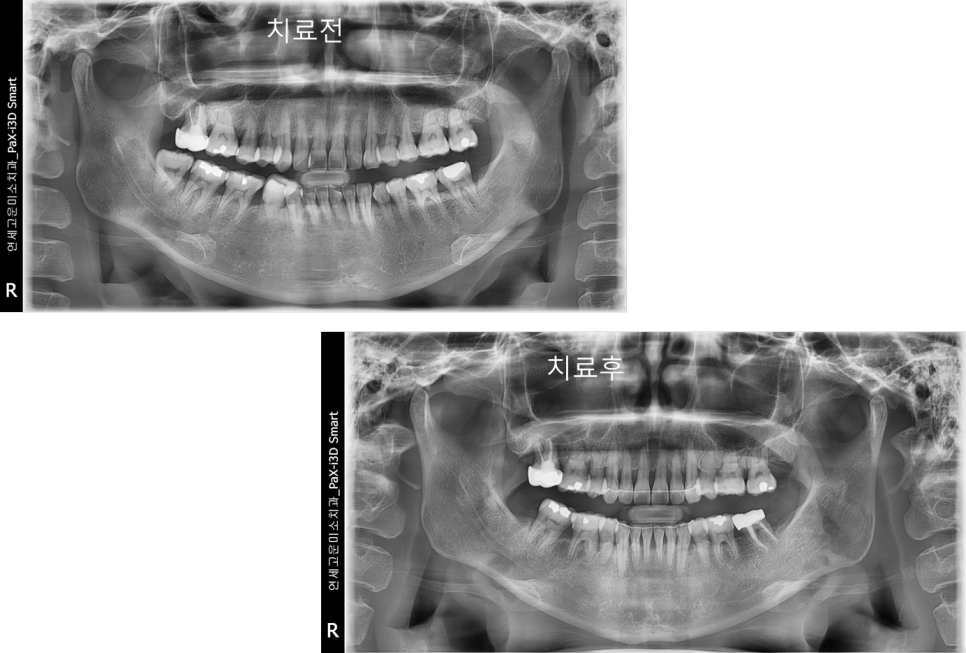

치료 전후 엑스레이입니다.

전과 후 치아배열도 좋아졌고

잇몸 건강도 잘 유지되고 있음을 보여줍니다.

부분교정 케이스) 임플란트를 하고 싶은데 공간이 없어요

치아가 빠지고 나서 오래 방치되면

옆에 치아들이 그 공간으로 쓰러지게 됩니다.

공간이 너무 많이 없어지면

쓰러진 치아를 신경치료하고 씌운 다음에

임플란트를 심게 되는데요. 그렇게 되면

건강한 치아를 깎아야 되고

임플란트를 하더라도 음식물도 많이 끼게 됩니다.

위에 환자분도 공간이 너무 많이 소실되어

큰 어금니를 심을 수 없을 뿐만 아니라

작은 어금니 공간도 되지 않는 상태입니다.

이런 경우 간단한 부분교정으로

해결할 수 있습니다

사랑니를 발치하고 간단한 교정장치를

이용하여 쓰러진 두 번째 큰 어금니를 세웠습니다

기간은 6개월 정도 소요되었습니다

완성된 모습입니다

옆치가 원래 각도 모습으로

잘 세워져있고

임플란트도 옆 치아의 뿌리와 나란히

잘 위치해 있는 것을 확인할 수 있습니다.